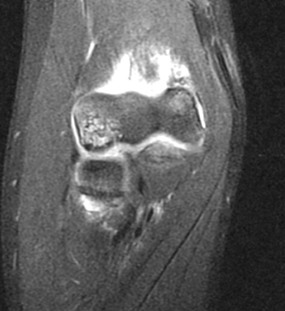

- MRI can help define stability of Grade II lesions

- Irregular contour or discontinuity of articular cartilage on MRI suggests unstable lesions

- CT scans and ultrasound can also help define size, location and stability of fragments

MRI demonstrates an unstable fragmented lesion within the capitellum